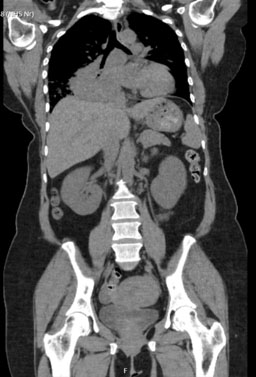

On admission, her laboratory results showed: elevated calcium (4.8 mmol/L), acute kidney injury (urea 17.3 and creatinine 176), a raised alkaline phosphatase (ALP) (168) with normal vitamin D (56) and PTH (1 pmol/L—appropriately suppressed). An electrocardiogram (ECG) showed normal sinus rhythm with left axis deviation, and an admission chest X-ray showed a large area of opacification in the right lung base. She was treated with intravenous fluids and received a first dose of zoledronic acid (4 mg intravenous). She underwent a computed tomography scan of her chest, abdomen and pelvis which showed a large right-sided pulmonary mass with maximum dimension of 8 cm, significant mediastinal lymphadenopathy and narrowing of the right main and lower lobe bronchus, and multiple bony metastases (Figure 1 and Figure 2). There was sparing of the left lung.

Figure 1: Axial image of CT Thorax with contrast (220 mA, 120 kV) showing large pulmonary mass with significant lymphadenopathy and mediastinal involvement, and near total collapse of the right lower lobe.